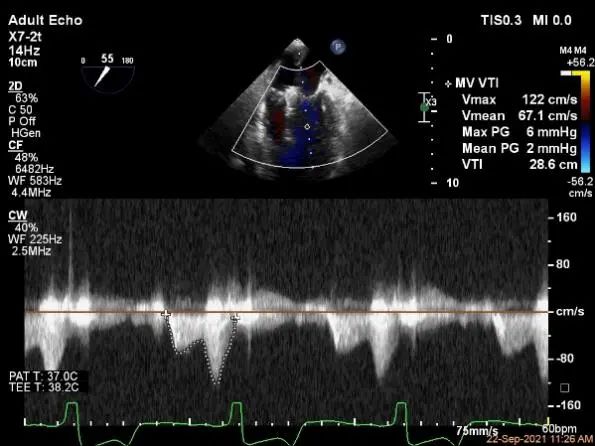

术中超声

P2区脱垂,宽14.8mm,Gap:3.3mm

3D-color,返流重度,3+级

麻醉状态下左肺静脉血流频谱

MVA:6.67cm²

评估瓣口条件,平均跨瓣压差:2mmHg,决定在第一个夹子外侧下第二个夹子

评估瓣口条件,平均跨瓣压差:4mmHg